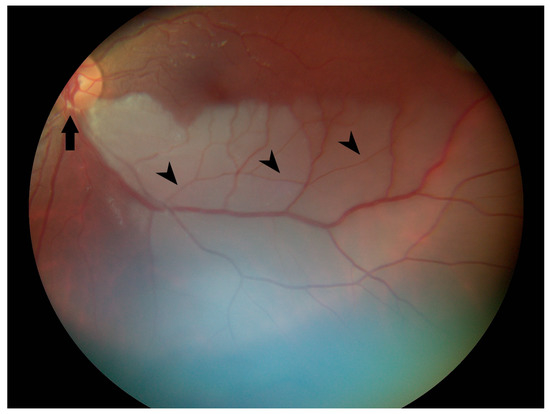

Ophthalmology was consulted after the vision changes did not resolve with 1000 mg of acetaminophen. Visual acuity was 20/20 in the right eye and 20/30 in the left eye. Pupils were equal, round, and reactive to light without relative afferent pupillary defect. Intraocular pressure was 10 mmHg in both eyes. Confrontational visual fields (via counting fingers) were normal in the right eye and revealed a superonasal defect in the left eye. Funduscopic exam of the right eye was normal, but in the left eye, there was frank whitening of the inferior half of the retina and a visible yellow refractile body within the inferior arterial arcade at the disc margin. Branches of the retinal artery downstream from this plaque were narrowed/attenuated (Figure 2). She was diagnosed with branch retinal artery occlusion (BRAO).

Figure 2. Color fundus photograph of the left eye at presentation shows retinal whitening of the inferior fundus consistent with diagnosis of branch retinal artery occlusion. Note the yellow refractile body within the inferior arterial arcade at the disc margin (arrow) and attenuation of peripheral arterioles (arrowheads).